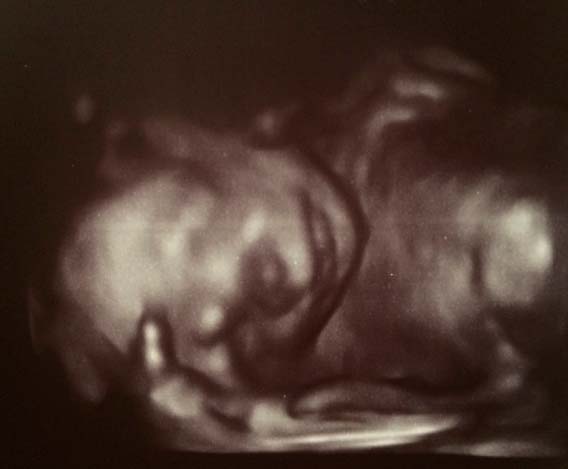

Se você não foi submetido a um ultrassom, o médico provavelmente prescreverá um encaminhamento. Durante o estudo, o médico irá verificar os parâmetros físicos do feto, verificar com os indicadores normativos da quantidade de líquido amniótico, verificar a condição da placenta.

Foto de ultrassom na semana 22